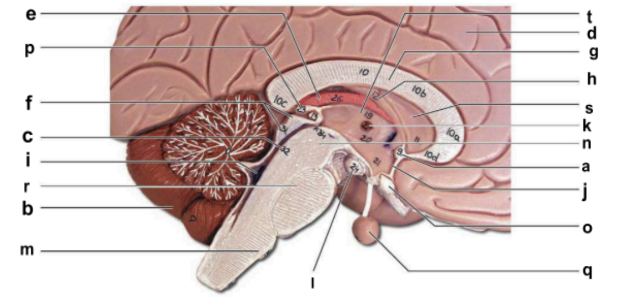

Identify the structure labeled “a” in the image.

anterior commissure

Identify the structure labeled “b” in the image.

cerebellum

Identify the structure labeled “c” in the image.

cerebral aqueduct

Identify the structure labeled “d” in the image.

cerebral hemisphere

Identify the structure labeled “e” in the image.

choroid plexus

Identify the structure labeled “f” in the image.

corpora quadrigemina

Identify the structure labeled “g” in the image.

corpos callosum

Identify the structure labeled “h” in the image.

fornix

Identify the structure labeled “i” in the image.

fourth ventricle

Identify the structure labeled “j” in the image.

hypothalamus

Identify the structure labeled “k” in the image.

interthalamic adhesion

Identify the structure labeled “l” in the image.

mammilary body

Identify the structure labeled “m” in the image.

medulla oblongata

Identify the structure labeled “n” in the image.

midbrain

Identify the structure labeled “o” in the image.

optic chiasma

Identify the structure labeled “p” in the image.

pineal gland

Identify the structure labeled “q” in the image.

pituitary gland

Identify the structure labeled “r” in the image.

pons

Identify the structure labeled “s” in the image.

septum pellucidum

Identify the structure labeled “t” in the image.

thalamus